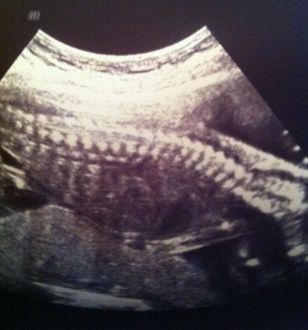

Echo 19ème semaine

Aujourd'hui le 4 Avril 2013, je me suis réveillée avec la tête remplie d'émotion car je sais que je vais te voir... Depuis bientôt 2 mois je ne t'ai pas vu dans l'écran...quelle hâte !!

Nous sommes arrivés à l'heure mais comme d'habitude, nous sommes pris avec 30 minutes de retard mais ça n'est pas grave car on sait que ton papa et moi allons te voir très vite.

Moment fatidique de la balance, ouf 4kg de pris en 5 mois de temps, je suis dans la normale mais devrait manger un peu plus, 2 repas par jour n'est pas forcément suffisant pour l’énergie que ta maman puise entre le travail 6jours / 7jours, ta croissance et les tâches ménagères !!

Le plus beau moment du rendez-vous, le moment où l'échographie se met en place et là ta maman se rend compte que tu as bien grandit malgrès le minuscule ventre qui ne veut pas pointer le bout de son nez, ta colonne vertébrale est formé, ton petit cœur bat très vite et tu remue beaucoup, c'est rigolo !! La gynécologue nous a bien montré ton estomac, tes reins, tes mains, tes pieds et tes petites oreilles et nous a bien confirmé que tu allais être un petit garçon... ( la joie de ton papa ), Mme la gynécologue nous a dit que tu étais un beau bébé qui se portait très bien... ( on adore ce genre de mots ).

Ton papa est toujours un peu en retrait lors de ces moments mais ta maman essaye de l'impliquer au maximum afin qu'il puisse lui aussi profiter pleinement de tous ces moments magiques !!

Nous devons prendre rendez-vous dans 3 semaines pour l’échographie du 2ème trimestre où là on va te mesurer et vérifier tous tes organes vitaux...